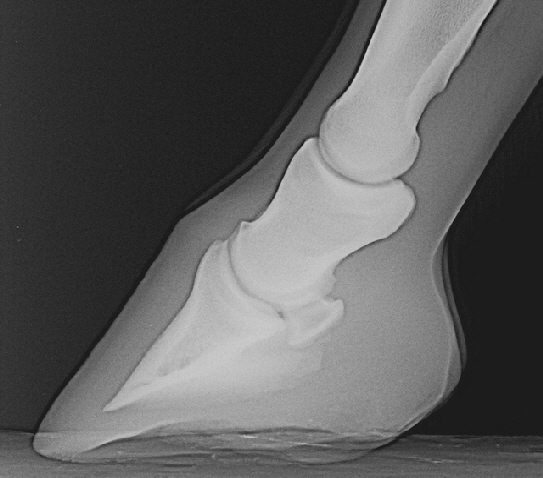

Normal Seitlich

ZeichngLatAuch auf der seitliche Aufnahme kann das Strahlbein beurteilt werden, da auch hier spezifische Veränderungen sichtbar werden. Auf der seitlichen Aufnahme ist das Strahlbein nur beurteilbar, wenn der Zentralstrahl genau auf das Strahlbein gerichtet ist. Überlagerungen des Hufknorpels bzw. des verknöcherten Hufknorpels müssen berücksichtigt werden. Diese Verknöcherungen liegen oft genau über dem Strahlbein und können mit Strahlbeinveränderungen verwechselt werden.

Bei jungen Pferden hat das Strahlbein eine quadratische bis trapezoide Form. Bei vielen Pferden zeigt sich eine kleine Verlängerung der Gleitfläche am oberen und unteren Rand des Strahlbeines.

Die Dicke der Gleitfläche beträgt etwa 2-3 mm. Eine leicht eingezogene Gleitfläche ist als normal anzusehen. Deutliche Ausziehungen am oberen oder unteren Rand sind krankhaft, tiefe scharfkantige Einbrüche in der Gleitfläche katastrophal. Am unteren Rand kann man unter der Gleitfläche oft den Eintritt der Gefäßkanäle sehen, gelegentlich kann man auch sehr ausgeprägte Strahlbeinkanäle nachvollziehen. Osteoporose und Sklerosierung sind bei dieser Aufnahme oft schwer zuverlässig zu beurteilen.

Eine spitze Ausziehung an der Gelenkfläche mit dem Hufgelenk ist meist klinisch bedeutungslos.

CR5Z18N0J230209

Strahlbein ohne Veränderungen, das Hufgelenk zeigt jedoch leichte Randausziehungen.